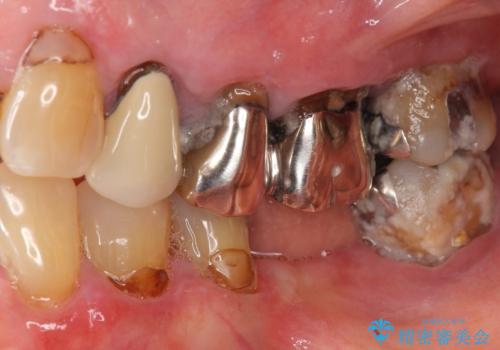

歯ぐきの腫れや出血が改善され、喜んで下さいました。

プラークコントロールを徹底して頂き、できるだけ歯が長持ちするよう今後も定期検診でフォローさせて頂きます。

被せ物の種類:メタルボンドクラウン エコノミー

入れ歯の種類:ノンクラスプデンチャー